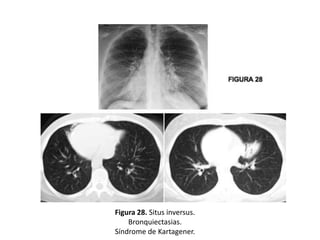

– Situs inversus (S. de Kartagener)

• Estenosis traqueal, bronquio traqueal, atresia bronquial

o secuestro pulmonar (Figuras 28 y 29).

Figura 28. Situs inversus.

Bronquiectasias.

Síndrome de Kartagener.